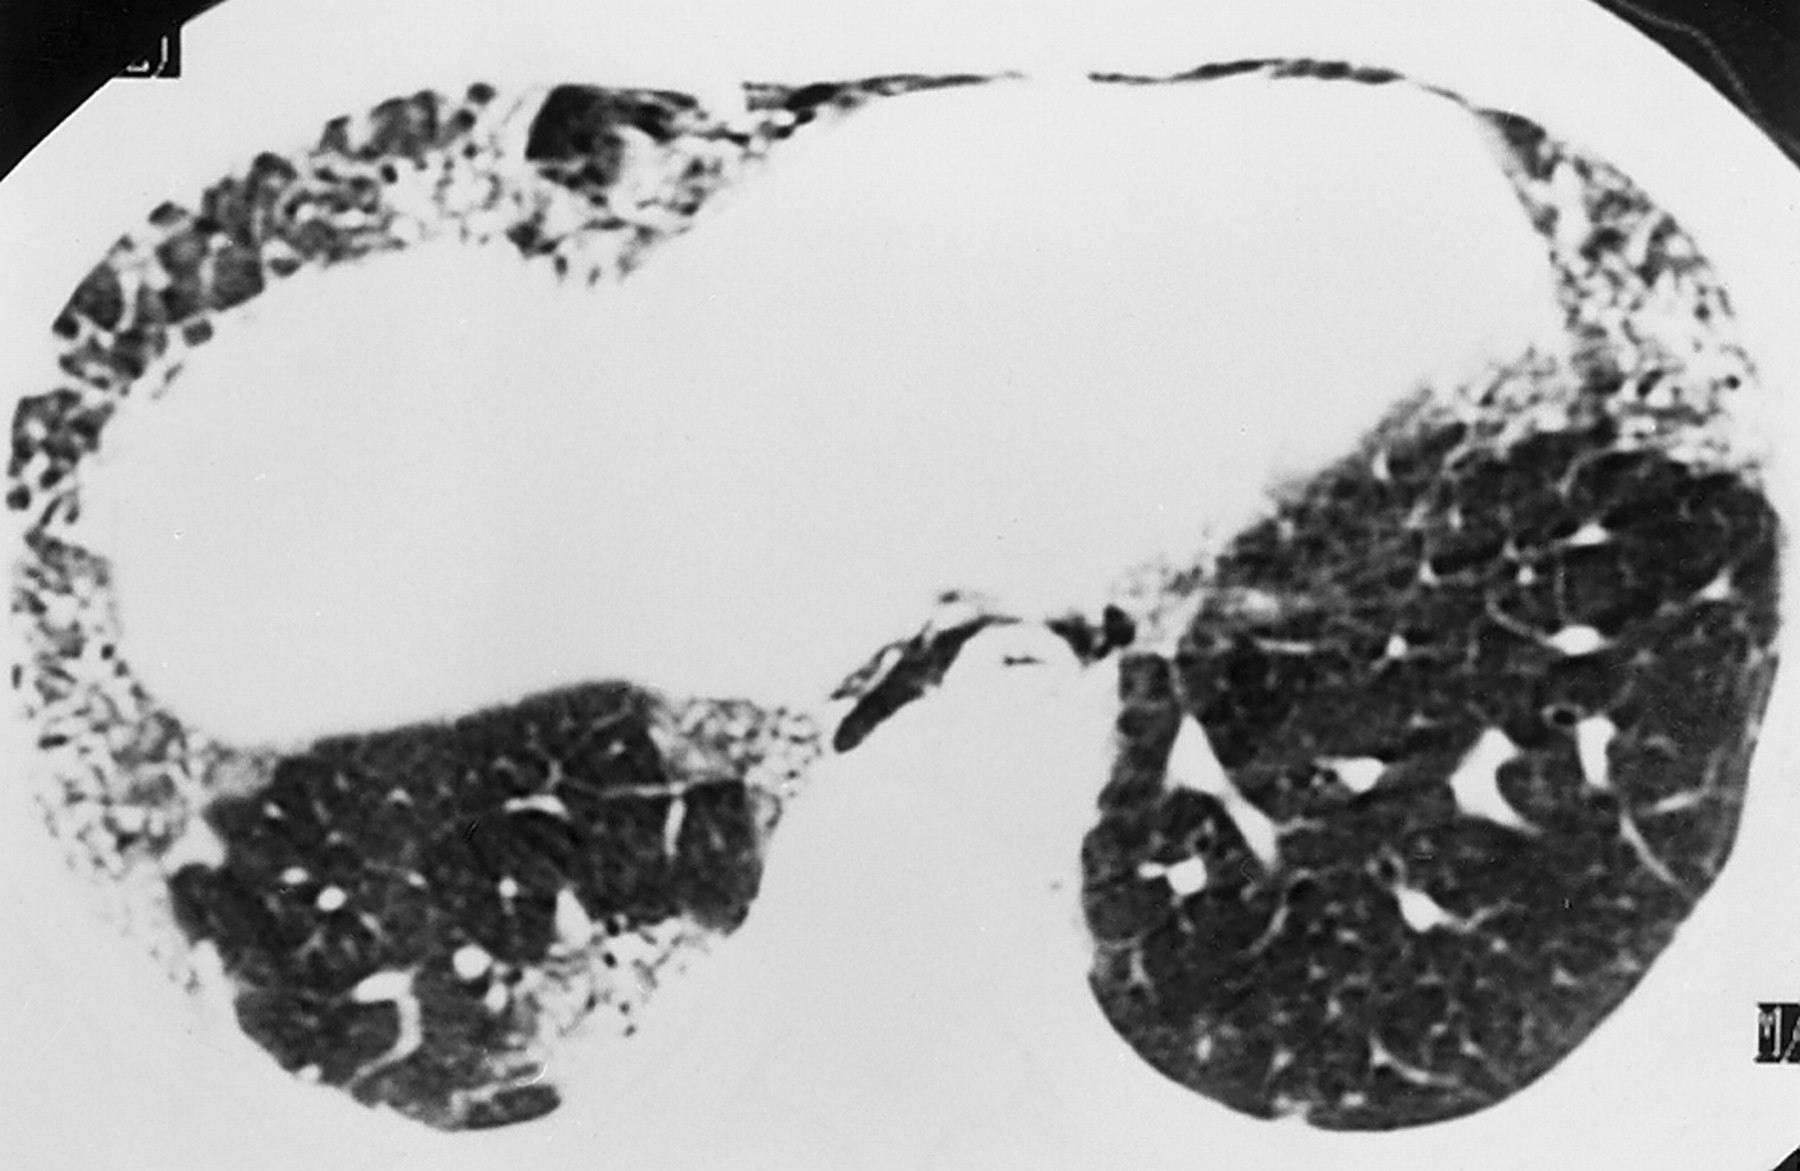

Пациент, будучи в нетрезвом состоянии взял паракват в рот, и затем выплюнул.

Отравления при вдыхании параквата.

Паракват - это гербицид, который используется в сельском хозяйстве во многих странах.